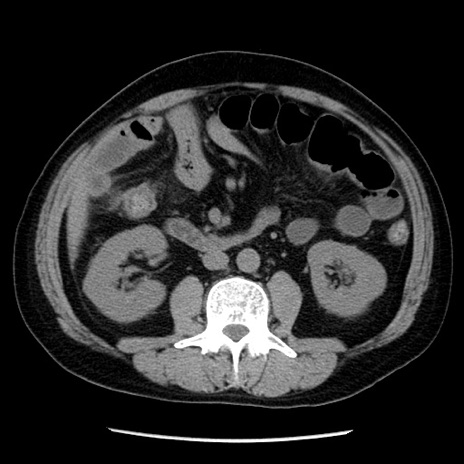

症例29(横断像)

【症例】40歳代男性

【現病歴】2日前から胃痛あり。徐々に周期的な激痛に変化した。本日になっても激痛があるため受診。

【身体所見】意識清明、BT 38-39℃台あり、腹部:膨満、やや硬、右下腹部に圧痛あり。

【データ】WBC 8500、CRP 23.26